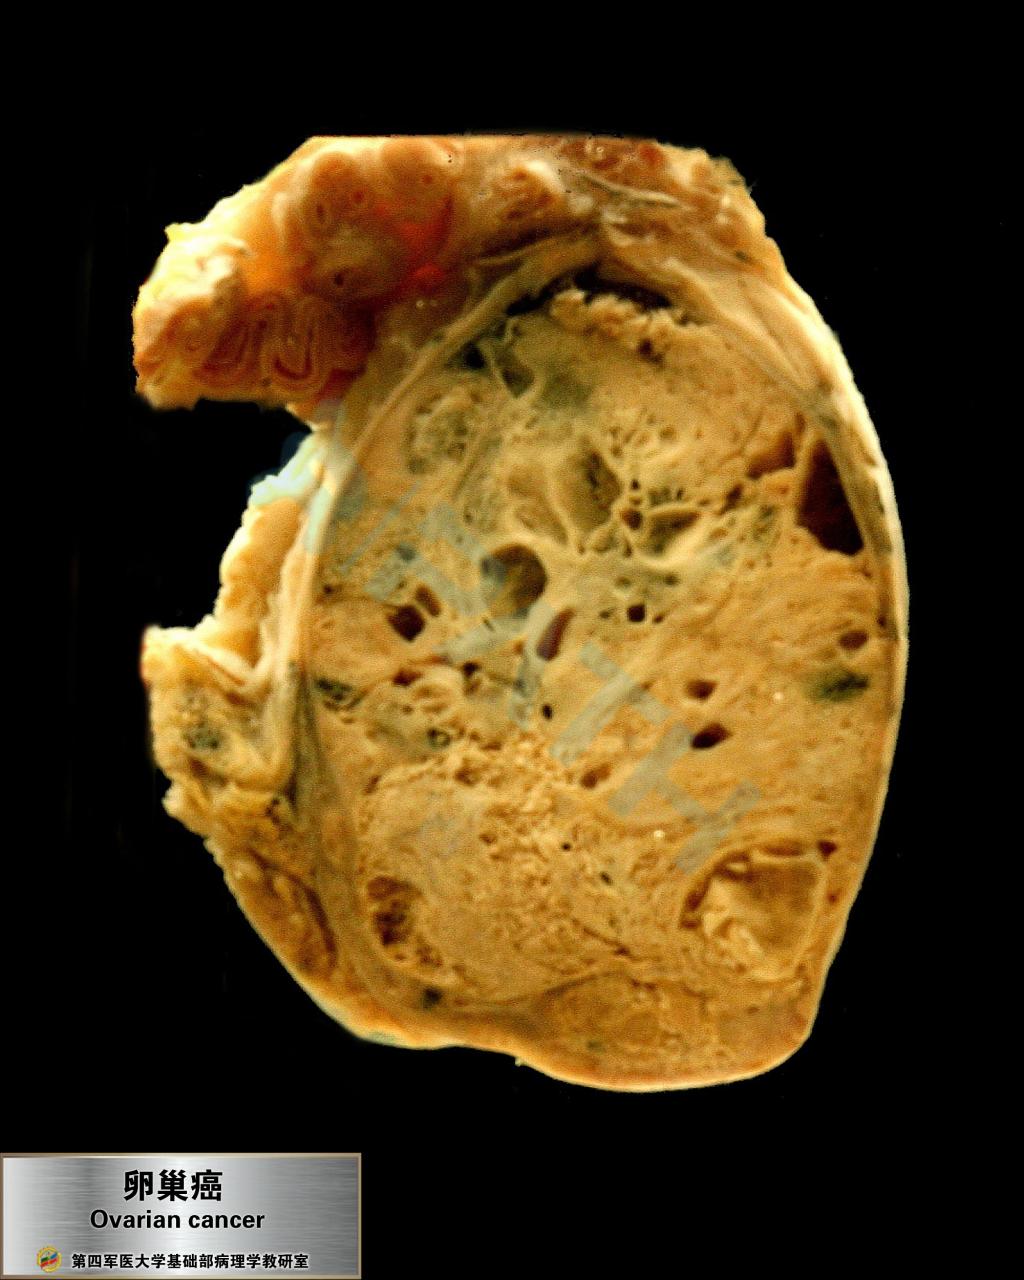

卵巢癌